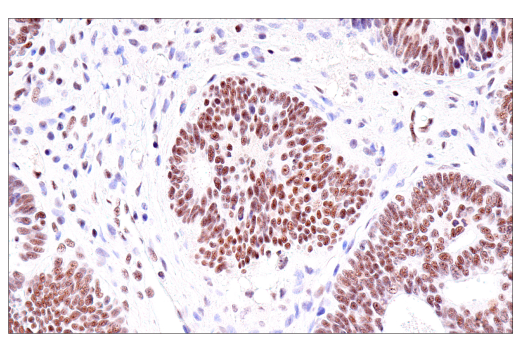

Immunohistochemical analysis of paraffin-embedded human endometrioid adenocarcinoma using USP39 (E8U2M) Rabbit mAb.

Immunohistochemistry Image 2: USP39 (E8U2M) Rabbit Monoclonal Antibody